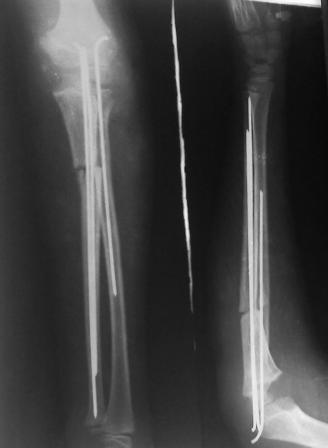

Иллюстрация к лечению застарелого повреждения Монтеджиа

Пациентка клиники детской травматологии ЦИТО

На рентненграмме видна деформация локтевой кости на границе верхней и средней трети. Ведь там был перелом.

Многоуважаемые коллеги, всем большое спасибо!!! Да, здесь было повреждение Монтеджиа, когда нарисовал скиаграмму все стало понятно. Мне очень понравились рекомендации Константина Требухина, только немножко видоизменил; я считал так, если деформацию исправить то локт/кость должна удлиниться, и во вторых, если на аппарате низвести лучевую кость, то может наступить позиционное несоответствие в дистальном радиоульнарном сочленении. 28.02.08г операция - шарнирная остеотомия локтевой кости на уровне деформации, далее вскрыт плечелучевой сустав, удалены рубцовые тканы, после исправления варусной деформации и создания физиологического изгиба локтевой кости головка луча легко вправился, из части рубцовой ткани сделана пластика кольцевндной связки, трансартикулярная фиксация спицей, локтевая кость двумя спицами.